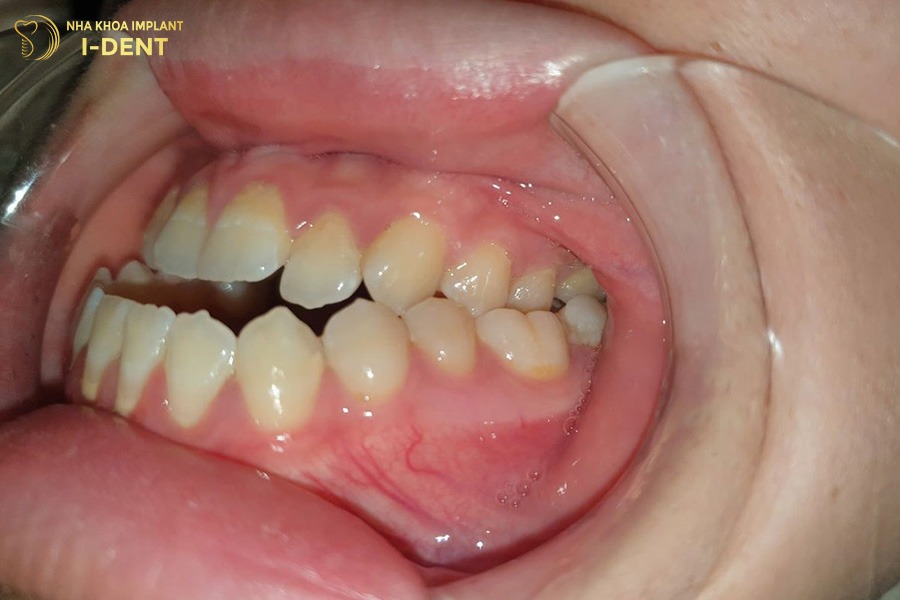

7. Hình ảnh trước và sau khi niềng răng móm

Dưới đây là hình ảnh của khách hàng điều trị răng móm tại Nha khoa I-Dent. Có thể thấy rõ sự thay đổi của khớp cắn, khuôn mặt và nụ cười sau khi niềng.

Hình ảnh trước và sau khi niềng răng móm tại Nha khoa I-Dent

Niềng răng giúp khắc phục hiệu quả tình trạng móm do răng gây ra

Sau khi niềng răng tại I-Dent, tình trạng móm răng được cải thiện rõ rệt